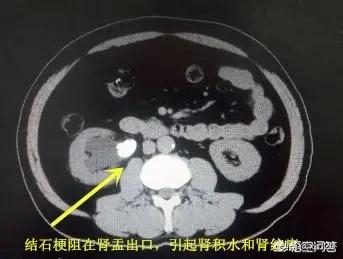

感谢邀请,回答下您这个问题,肾结石需不需要碎石,主要还是看结石有没有造成梗阻李高启。如果肾结石位于肾盂输尿管连接部,引起了肾积水,肯定需要尽快处理,包括体外碎石,输尿管镜、软镜碎石,经皮肾镜碎石等方式。

肾结石需不需要急着碎石?结石大小是一个方面,主要还是看结石有没有造成梗阻,有些人输尿管狭窄,5mm的结石可能不会自行排出,引起梗阻,这时候需要要积极处理,避免长时间积水损害了肾功能,这种损害一般是不可逆的李高启。